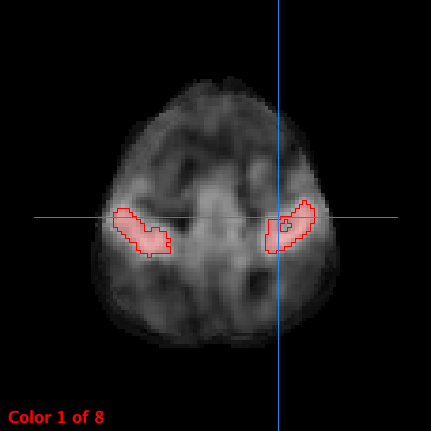

功能性磁振造影